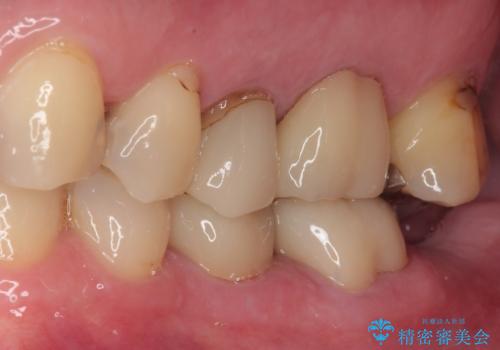

歯と歯茎の間に圧排糸と言われる糸を入れてシリコーン印象材にて精密な型どりをしました。

セラミックインレーの装着時には、唾液の侵入を防ぐために、ラバーダム防湿を行いました。